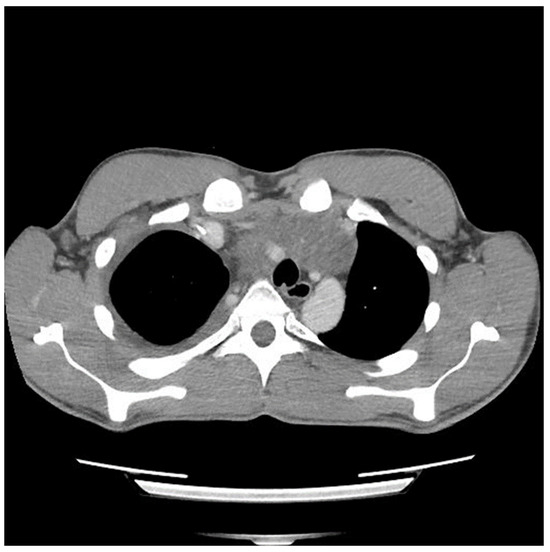

A 29-year-old male with no previous medical history presented to the emergency department in May 2021 with symptoms of acute appendicitis. He was ultimately found to have a large mediastinal mass (Figure 1). A needle biopsy indicated predominantly mature teratomas with some elements of a yolk sac tumor (YST). Biochemical workup revealed an initial alpha fetal protein (AFP) level of 1654.51 ng/mL, and the beta human chorionic gonadotropin (β-HCG) level was slightly elevated at 7.2 (IU/L).

Figure 1.

Computed tomography (CT) scan image of mediastinal mass at the time of initial presentation.